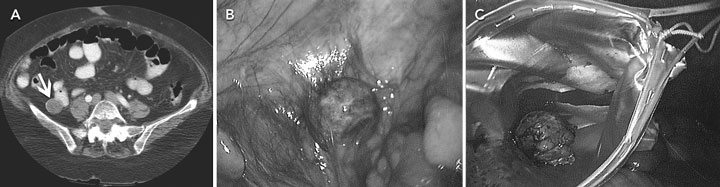

Laboratory investigations showed a serum lipase concentration of 393 U/L (reference range, 114–286 U/L) with normal white blood cell count. Abdominal computed tomography revealed a 2.8 × 2.4 cm mass in the right lower quadrant, with a calcific rim and foci of calcium within the lesion (Figure, A). The mass appeared to be outside the small bowel, suggesting a mucocele or mucoid tumour. Laparoscopy revealed a 2.5 cm solid mass containing a gallstone (Figure, B and C). The drainage from the umbilicus continued after surgery and was apparently unrelated to the spilled gallstone.